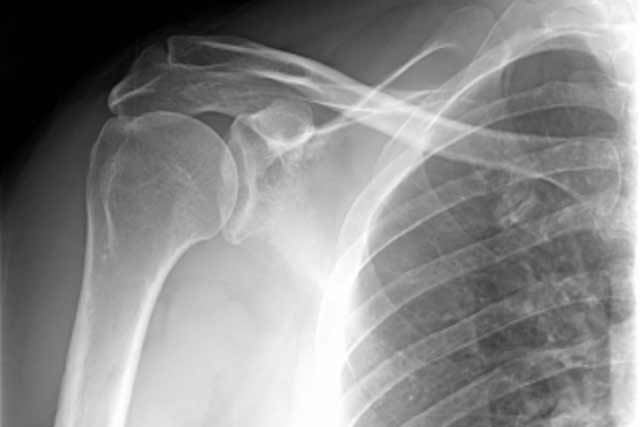

Problems affecting the shoulder and elbow are widespread and can cause pain and a loss of ability to perform daily tasks, work and sporting activities.

We have a specialist team of staff who are dedicated to the diagnosis, investigation and treatment of all shoulder and elbow problems. We are a tertiary centre and accept referrals for specialist opinions in surgical and non-surgical cases.